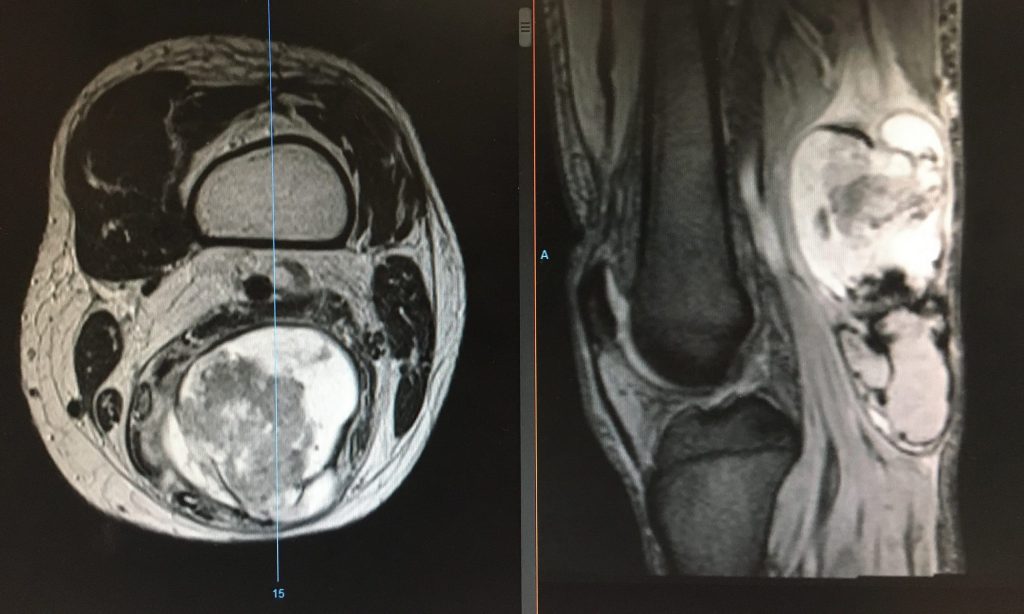

Los tumores pueden desarrollarse en los huesos o en los tejidos blandos (músculos, tendones, grasa, vasos sanguíneos, etc.). Pueden ser:

Malignos (sarcomas): tumores agresivos que pueden diseminarse a otras partes del cuerpo. Requieren tratamiento quirúrgico especializado, y a menudo quimioterapia o radioterapia.

Sarcomas óseos o de partes blandas (osteosarcoma, condrosarcoma, liposarcoma, etc.)